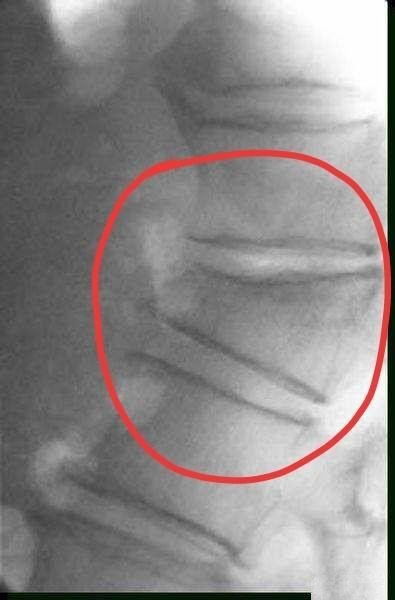

压缩性骨折就好比一个馒头被压扁了,但是又没有整个四分五裂,还是大致原来的环形轮廓。如果四分五裂了,那就是压缩性粉碎性骨折。

压缩性骨折经常出现于老年人,因为老年人的骨质疏松而导致骨质的强度明显减小,当受到垂直方向的暴力,会导致骨质的压缩变扁,从而出现压缩性骨折。

出现此类的情况多见于严重骨质疏松的老人在弯腰或者抬重东西的时候出现腰椎和胸椎的压缩性骨折。会即刻出现胸闷腰痛直不起腰,或者隐隐作痛,如果压缩性骨折并不是很严重的话,也很容易被遗漏。尤其是农村的留守老人,子女在外地工作的,来医院并不方便,所以多选择在家里面忍一忍。可随着时间的延长,疼痛并没有好转,再来医院检查的时候,骨折已经变成陈旧性的了。

有极少部分的骨折,并不会有明显的疼痛,或者只痛几天就好转了。但并不代表骨折恢复了。椎体的骨折一般要求:压缩小于1/2的可以保守治疗,卧床休息2到3个月,在医生的指导下逐渐的恢复坐立和行走。大于1/2的压缩性骨折是需要做手术的,目前常采用的治疗方案是pvp、pkp,是一种非常经济实用,效果好的治疗方案,比过去做钢板螺钉,撑开植骨要简单的多,但是任何手术方式都有它的缺点,具体情况也要具体分析。